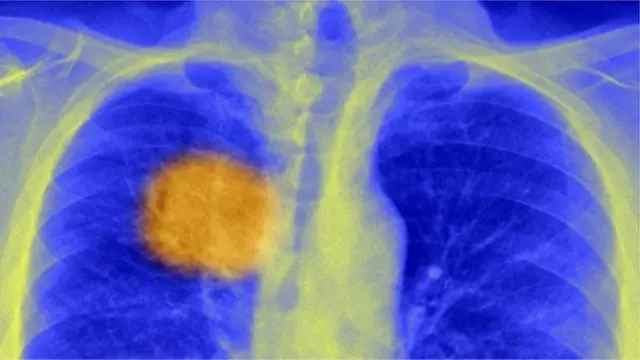

Akciğer kanseri nasıl teşhis edilir?

Teşhis genellikle röntgen, BT taraması ve bronkoskopi gibi görüntüleme yöntemleri ile birlikte biyopsi ile yapılır.